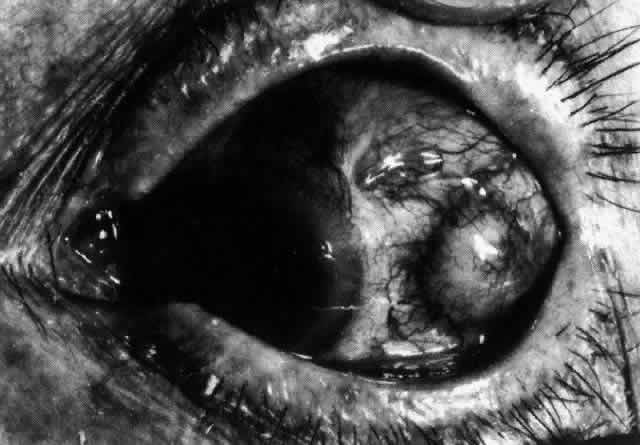

Necrotizing anterior scleritis without adjacent inflammation appears to be a well-defined condition with little relation in clinical features to necrotizing scleral disease, even though the pathology is similar and the final result is the same. Scleromalacia perforans is characterized by the almost total lack of any symptoms. It occurs almost exclusively in patients with long-standing polyarticular rheumatoid arthritis, the majority of whom are female (Figs. 49 and 50; Color Plate 1E).

Fig. 49. A white necrotic plaque developing in an area of sclera with practically no surrounding inflammation in a 60-year-old woman who had had Crohn's disease for 17 years.

Fig. 50. Scleromalacia perforans after treatment. The very thin sclera is covered by conjunctiva only and a few remaining large blood vessels. (Courtesy of Mr. HE Hobbs)

The anterior sclera loses its covering of episclera and develops an area of yellow-white necrotic slough over many months; this eventually separates or is absorbed, leaving the underlying choroid covered by either conjunctiva or nothing at all. As with necrotizing disease, the choroid does not bulge into this ectatic area; but unlike necrotizing disease, spontaneous healing of even small perforations is very limited once the necrotic tissue has been removed (see Fig. 50).